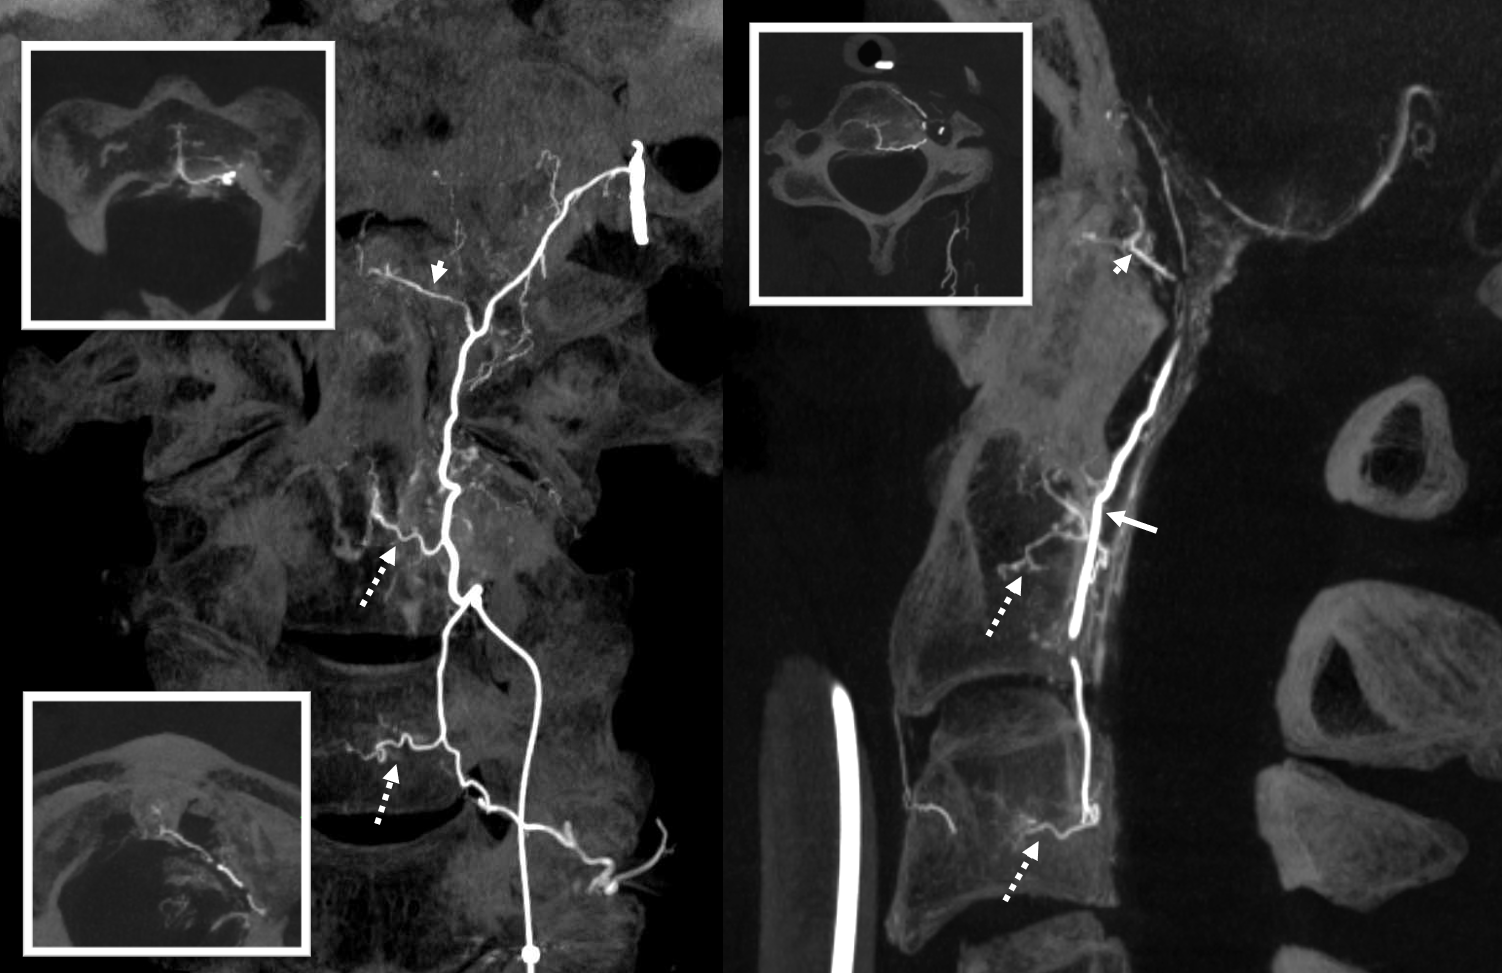

Fusion of two vertebral artery Cone Beam CT injections demonstrating both odontoid arcades (solid green and red arrows), and the intersegmental epidural connections between them (dashed arrows). At the apex of the arcade, supply to the ligamentous / adipose tissues around the dens is also present (arrowheads)

Of course, they do exist – in this relatively safer territory there will always be things to watch out for. In the same case, we see below the left odontoid arcade (arrow) connecting via epidural branch (dashed arrow) to a likely dural branch in the C3 nerve root sleeve (arrowhead). It is a thinner branch and separate from the more prominent beautifully seen ventral (solid open arrow) and dorsal (dashed open arrow) radicular branches which supply the C3 nerve and lateral cord. Both the nerve root sleeve (arrowhead) and radicular branches arise from the common C3 segmental artery (ball arrow). Therefore, injection of embolic material (liquid embolic especially) should be done with care.